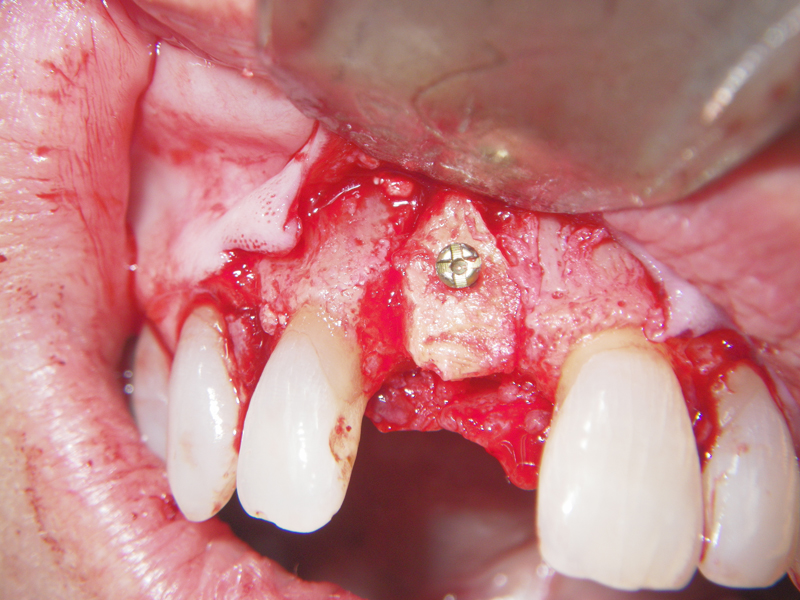

- Stage I: Implant placement/Sealing Screw

- Alveolar Ridge Augmentation

- Blockgraft